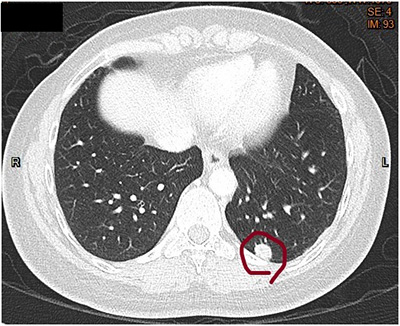

70歲女性7年前接受大腸癌手術,術後沒有接受任何輔助性治療,癌症指數也沒有上升,追蹤時發現左下肺結節,經手術切除確診為第一期肺腺癌,並非大腸癌合併肺部轉移。

34歲女性患有乳癌合併肺部轉移,經治療後發現大部分肺部結節消失不見唯獨左下肺結節並沒有變化,術後證明仍然是乳癌合併肺部轉移,而且其分子生物學特性與當初診斷時的乳癌有不一樣的地方,經過調整治療後病患仍存活至今,目前無證據復發。

36歲女性直腸癌合併支氣管及肺部轉移,因腫瘤讓呼吸道阻塞,造成嚴重呼吸困難,經過支氣管鏡腫瘤燒灼術後症狀達到緩解,並積極接受抗腫瘤治療,包括手術切除、標靶治療、化學治療及放射線治療等,腫瘤已達到控制,之後病患也接受肺部轉移處切除手術當作輔助治療,目前病情穩定,並無復發跡象。